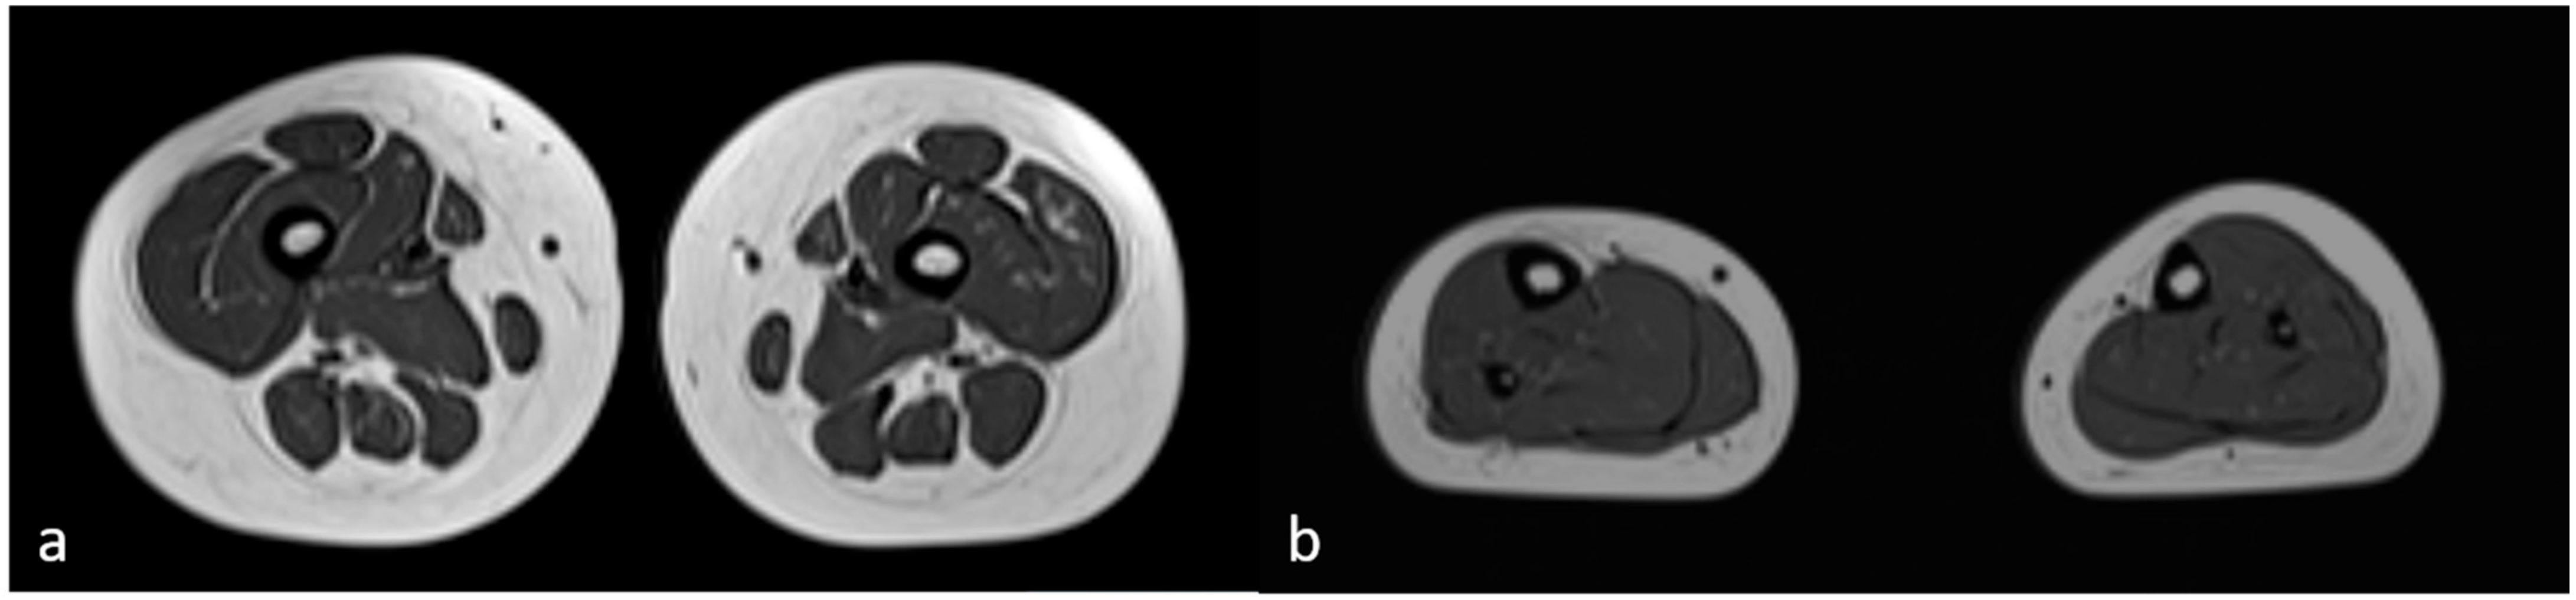

3.1. Clinical Findings